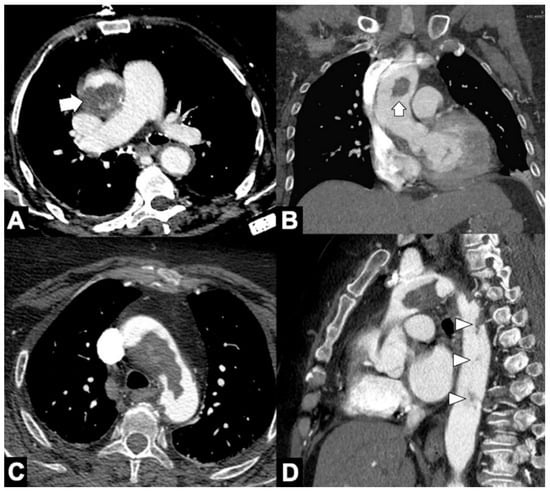

| Location | CTA Findings | Complete Rupture | Impending Rupture |

|---|---|---|---|

| Intramural | Increased aneurysm (>5.5 cm) | - | + |

| Rapid enlargement rate (>4 mm/year) | - | + | |

| Focal wall irregularity | + | + | |

| Hyperattenuating crescent sign | - | + | |

| Thrombus fissuration | - | + | |

| Draped Aorta sign | - | + | |

| Missing calcium sign | - | + | |

| Tangential calcium sign | - | + | |

| Luminal | Aortoesophageal fistula | + | - |

| Aortobronchial fistula | + | - | |

| Periaortic stranding | - | + | |

| Extraluminal | Contrast extravasation | + | - |

| Mediastinal hematoma | + | - | |

| Pleural hematoma | + | - | |

| Pericardial hematoma | + | ± |